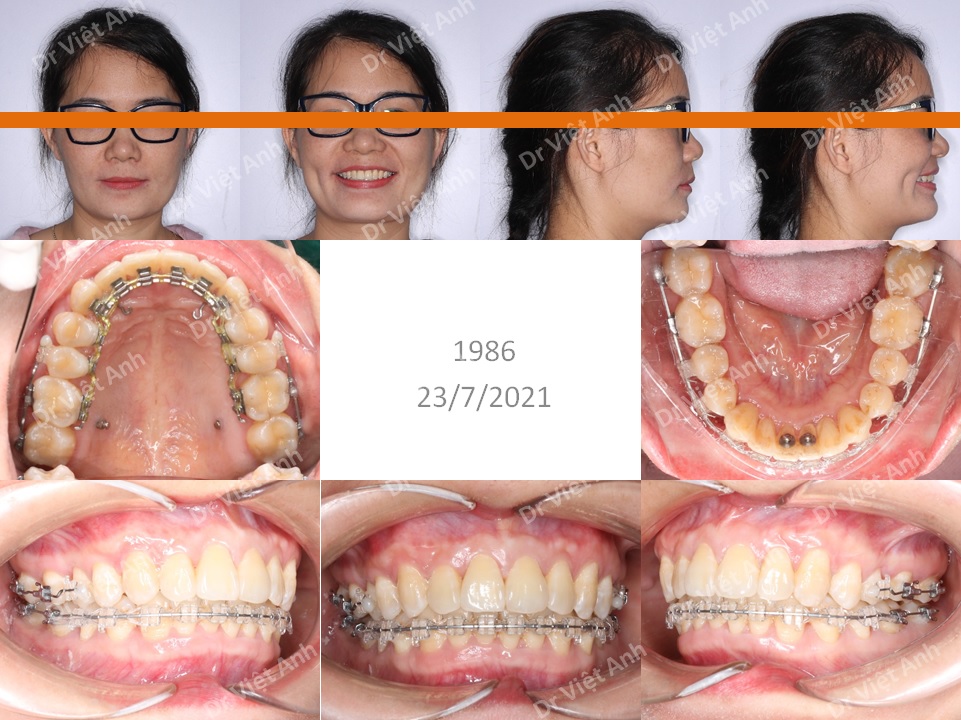

Tình trạng trước khi niềng răng tại trung tâm niềng răng chuyên sâu thạc sĩ bác sĩ nội trú Việt Anh: răng hai hàm hơi lộn xộn, khớp cắn sâu

Phương án niềng răng mặt trong: không nhổ răng, mài kẽ hai hàm, di xa hàm trên để khắc phục khớp cắn sâu, dùng mắc cài mặt lưỡi hàm trên và mắc cài pha lê hàm dưới (Hàn Quốc)

Phương án niềng răng mặt trong: không nhổ răng, mài kẽ hai hàm, di xa hàm trên để khắc phục khớp cắn sâu, dùng mắc cài mặt lưỡi hàm trên và mắc cài pha lê hàm dưới (Hàn Quốc)

Kết quả niềng răng mặt trong: răng đều đẹp cân đối, khớp cắn lồng múi tốt

So sánh ảnh trước và sau niềng răng mặt trong: răng đều hơn, răng cửa hàm trên không còn chìa nhiều so với hàm dưới, khớp cắn không bị sâu nữa, nụ cười đẹp hơn